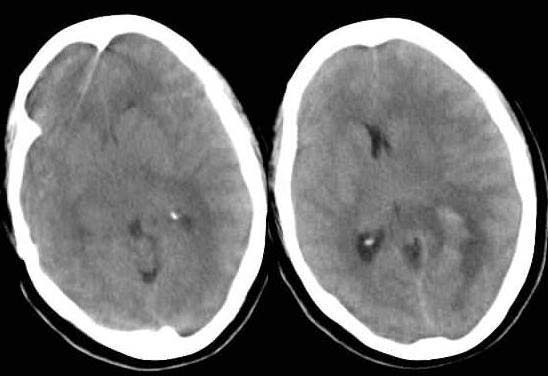

患者 女 52岁 头痛,右肢瘫痪14小时,查体:右上下肢肌力0级,血压120mmhg/80mmhg

左顶后脑出血{影像报告},至于原因结合临床吧!!!

右顶部脑出血,原因?

左枕顶脑血肿;血肿密度不均,可能为多次少量出血所致。

原因有5:1.出血灶位于左枕顶叶,但大脑镰中后部偏下方仅有轻微向右移位,偏上方则向左侧有移位。2.出血灶密度明显不均匀,见有较广泛小泡状以及一个较大呈枣核样低密度区,且出血灶形态不规则,边缘模糊。3.出血灶周围水肿带明显不符合一般出血的特点。出血灶最大径在中后部,而其内、后部基本没有水肿带;相反水肿带却出现在外、前部,以外部更显著。且,水肿带之密度、出现时间等均不符合一般的出血。4.大脑镰中前部之偏下方明显向右移位,左侧基底节、丘脑、左侧脑室等均向右侧明显移位,左侧侧脑室大部分受压、闭塞。它们的移位,用左枕、顶叶出血灶之推压来解释显然行不通。5.左侧额、顶、枕部灰质密度、形态、走向、分步均明显异常,呈团片状、指状且略高于对侧。综上所诉,我考虑为瘤卒中,建议增强或mri检查。左侧胶质母细胞瘤可能性最大。第2考虑转移瘤